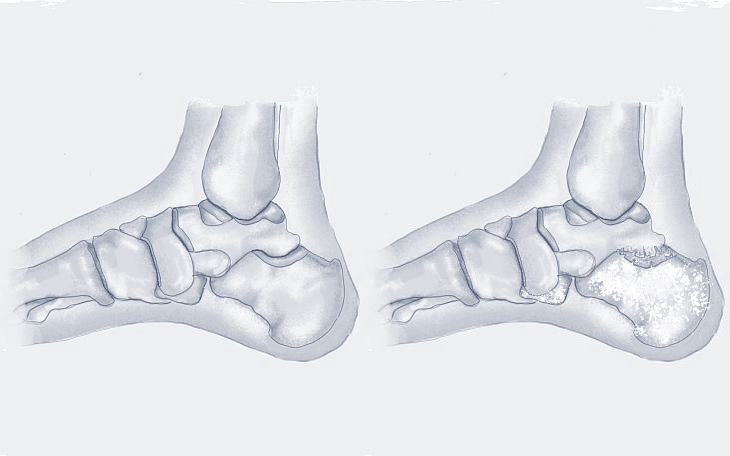

Links: Vollständiger Knorpelverlust mit Aufhebung des Gelenkspalts

Rechts: Postoperatives Bild nach Implantation der OSG-TEP

Wann wird Endoprothetik empfohlen?

Eine Endoprothese am Sprunggelenk wird empfohlen, wenn der Gelenkverschleiß (Arthrose) so weit fortgeschritten ist, dass konservative Maßnahmen wie Einlagen, Orthesen oder Infiltrationen keine ausreichende Schmerzlinderung mehr bieten. Typische Indikationen sind eine schwere Sprunggelenksarthrose nach Verletzungen oder Fehlstellungen.